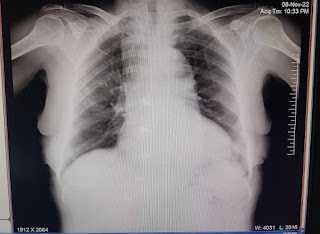

Chest x ray PA view